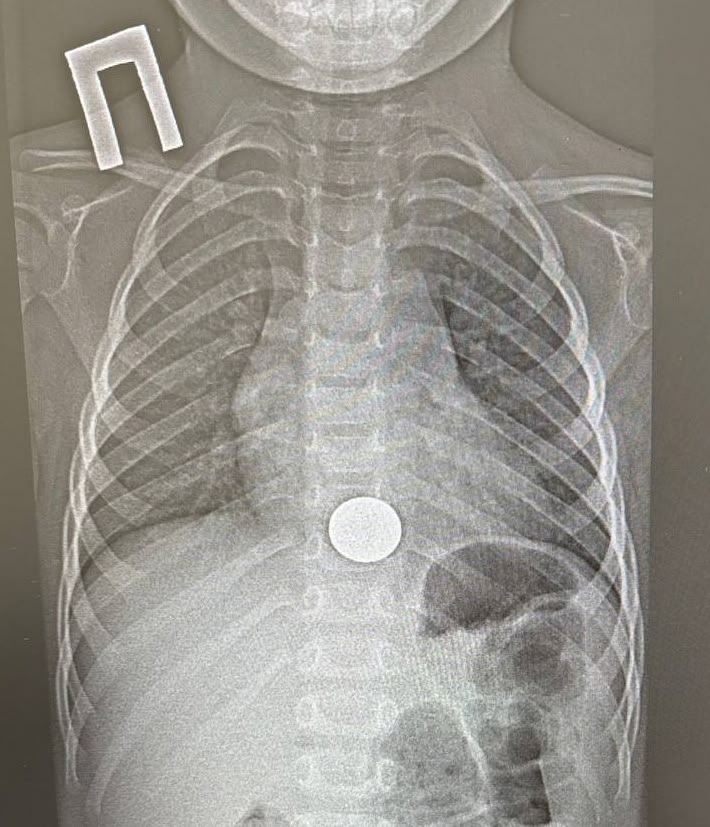

В Татарстане ребенок проглотил монету и попал в больницу. Об этом сообщает пресс-служба ГАУЗ НДРБ с ПЦ.

Инцидент произошел 15 декабря. Малолетний взял у старшего брата монету, чтобы поиграть с ней, и случайно ее проглотил. Ребенок сразу рассказал об этом родителям, и мать оперативно доставила его в больницу. Мальчик жаловался на боль за грудиной.

Пациенту провели рентген и обнаружили у него инородное тело в пищеводе, детский врач выполнил эндоскопическое удаление монетки. Вся процедура заняла около минуты.